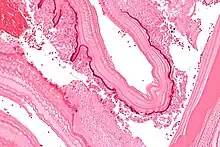

From the embryo released from an egg develops a hydatid cyst, which grows to about 5–10 cm within the first year and is able to survive within organs for years.[25] Cysts sometimes grow to be so large that by the end of several years or even decades, they can contain several liters of fluid. Once a cyst has reached a diameter of 1 cm, its wall differentiates into a thick outer, non-cellular membrane, which covers the thin germinal epithelium. From this epithelium, cells begin to grow within the cyst. These cells then become vacuolated, and are known as brood capsules, which are the parts of the parasite from which protoscolices bud. Often, daughter cysts also form within cysts.[24]

The cysts found in those with cystic echinococcosis are usually filled with a clear fluid called hydatid fluid, are spherical, and typically consist of one compartment and are usually only found in one area of the body. While the cysts found in those with alveolar and polycystic echinococcosis are similar to those found in those with cystic echinococcosis, the alveolar and polycystic echinococcosis cysts usually have multiple compartments and have infiltrative as opposed to expansive growth.[11][12]